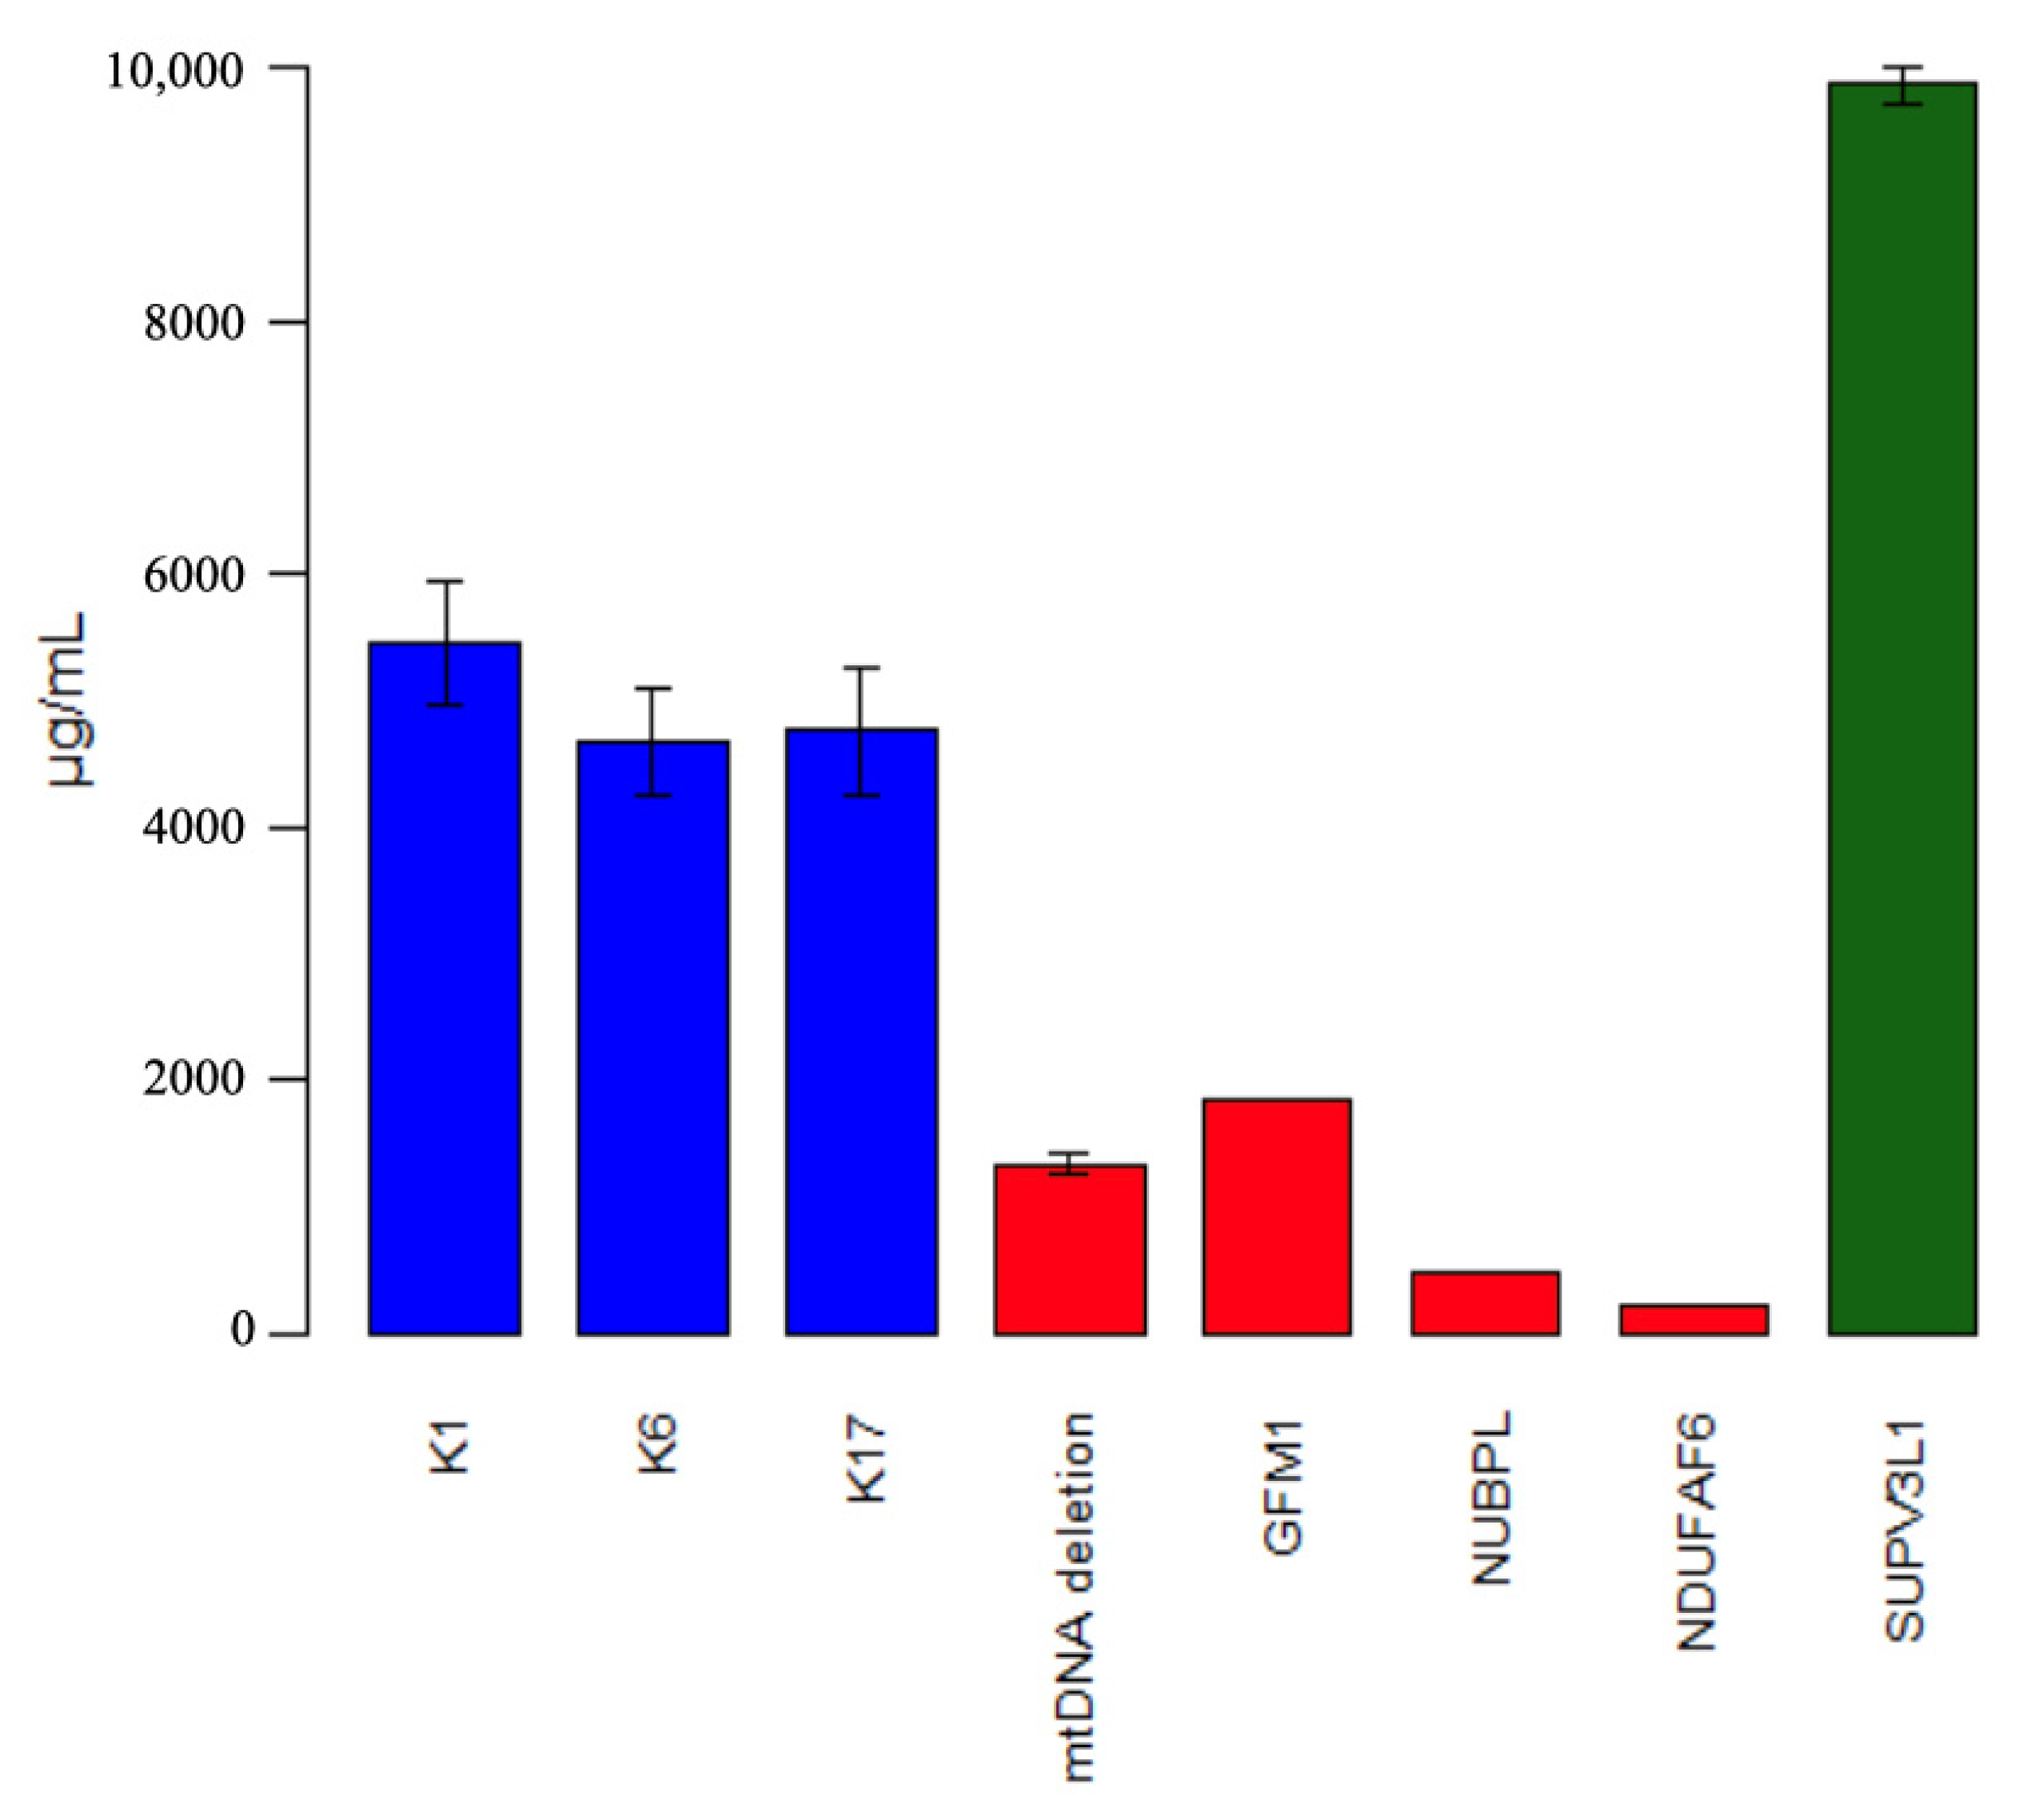

3.4. Complex 1 Content